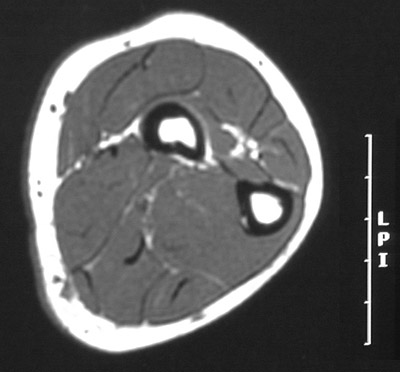

This is a normal axial T1 weighted MRI scan demonstrating the Radius, marrow cavity and Compact or cortical bone and Ulna and Abductor pollicis longus and Extensor carpi ulnaris and Extensor digitorum communis and Extensor carpi radialis brevis and Extensor carpi radialis longus and Supinator and Brachioradialis and Pronator teres and Flexor pollicis longus and Flexor carpi radialis and Palmaris longus and Flexor digitorum superficialis and Flexor carpi ulnaris and and Flexor digitorum profundus.